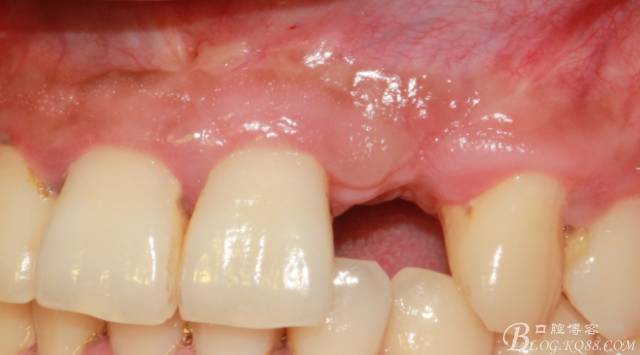

事實(shí)證明,我的做法沒(méi)有錯(cuò)誤,一個(gè)月后,軟組織健康愈合。鄰牙軟組織沒(méi)有退縮。

再次翻瓣。